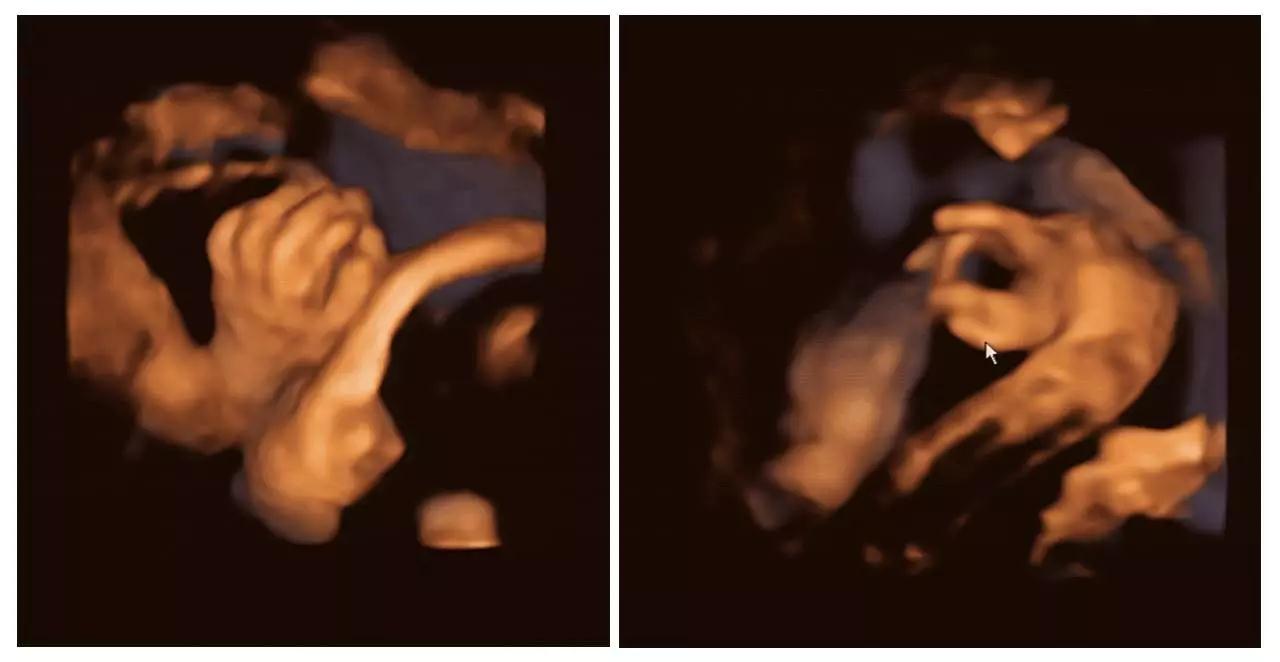

艾玛妇产成功筛查胎儿畸形的案例(部分)——

(右手多指畸形)

(单侧唇裂)

(双侧唇裂)